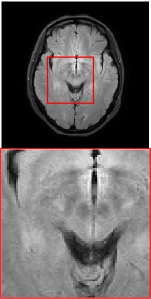

Figure 5 provides the qualitative comparison of the various methods on the four datasets at a scale of 4. The top, second, third, and bottom rows are the SR results under the FastMRI, clinical brain, clinical tumor and clinical pelvic datasets, respectively. The red boxes indicate the zoom-in region of complicated anatomical structures along with their corresponding error maps. Note that the brighter textures in the error maps, the lower the quality of the reconstructed images. As can be seen, compared to methods based on Transformers and CNNs, diffusion-based methods like DisC-Diff and DiffMSR (Ours) are capable of reconstructing high-realistic images with promising reconstruction metric scores (PSNR and SSIM). Nevertheless, while DisC-Diff can reconstruct high-precision MR images, it does not preserve the structure present in the original HR images, introducing some additional information that can affect medical diagnosis. In contrast, our method combines DM and PLWformer, which can preserve the original image’s structure while restoring high-frequency information.